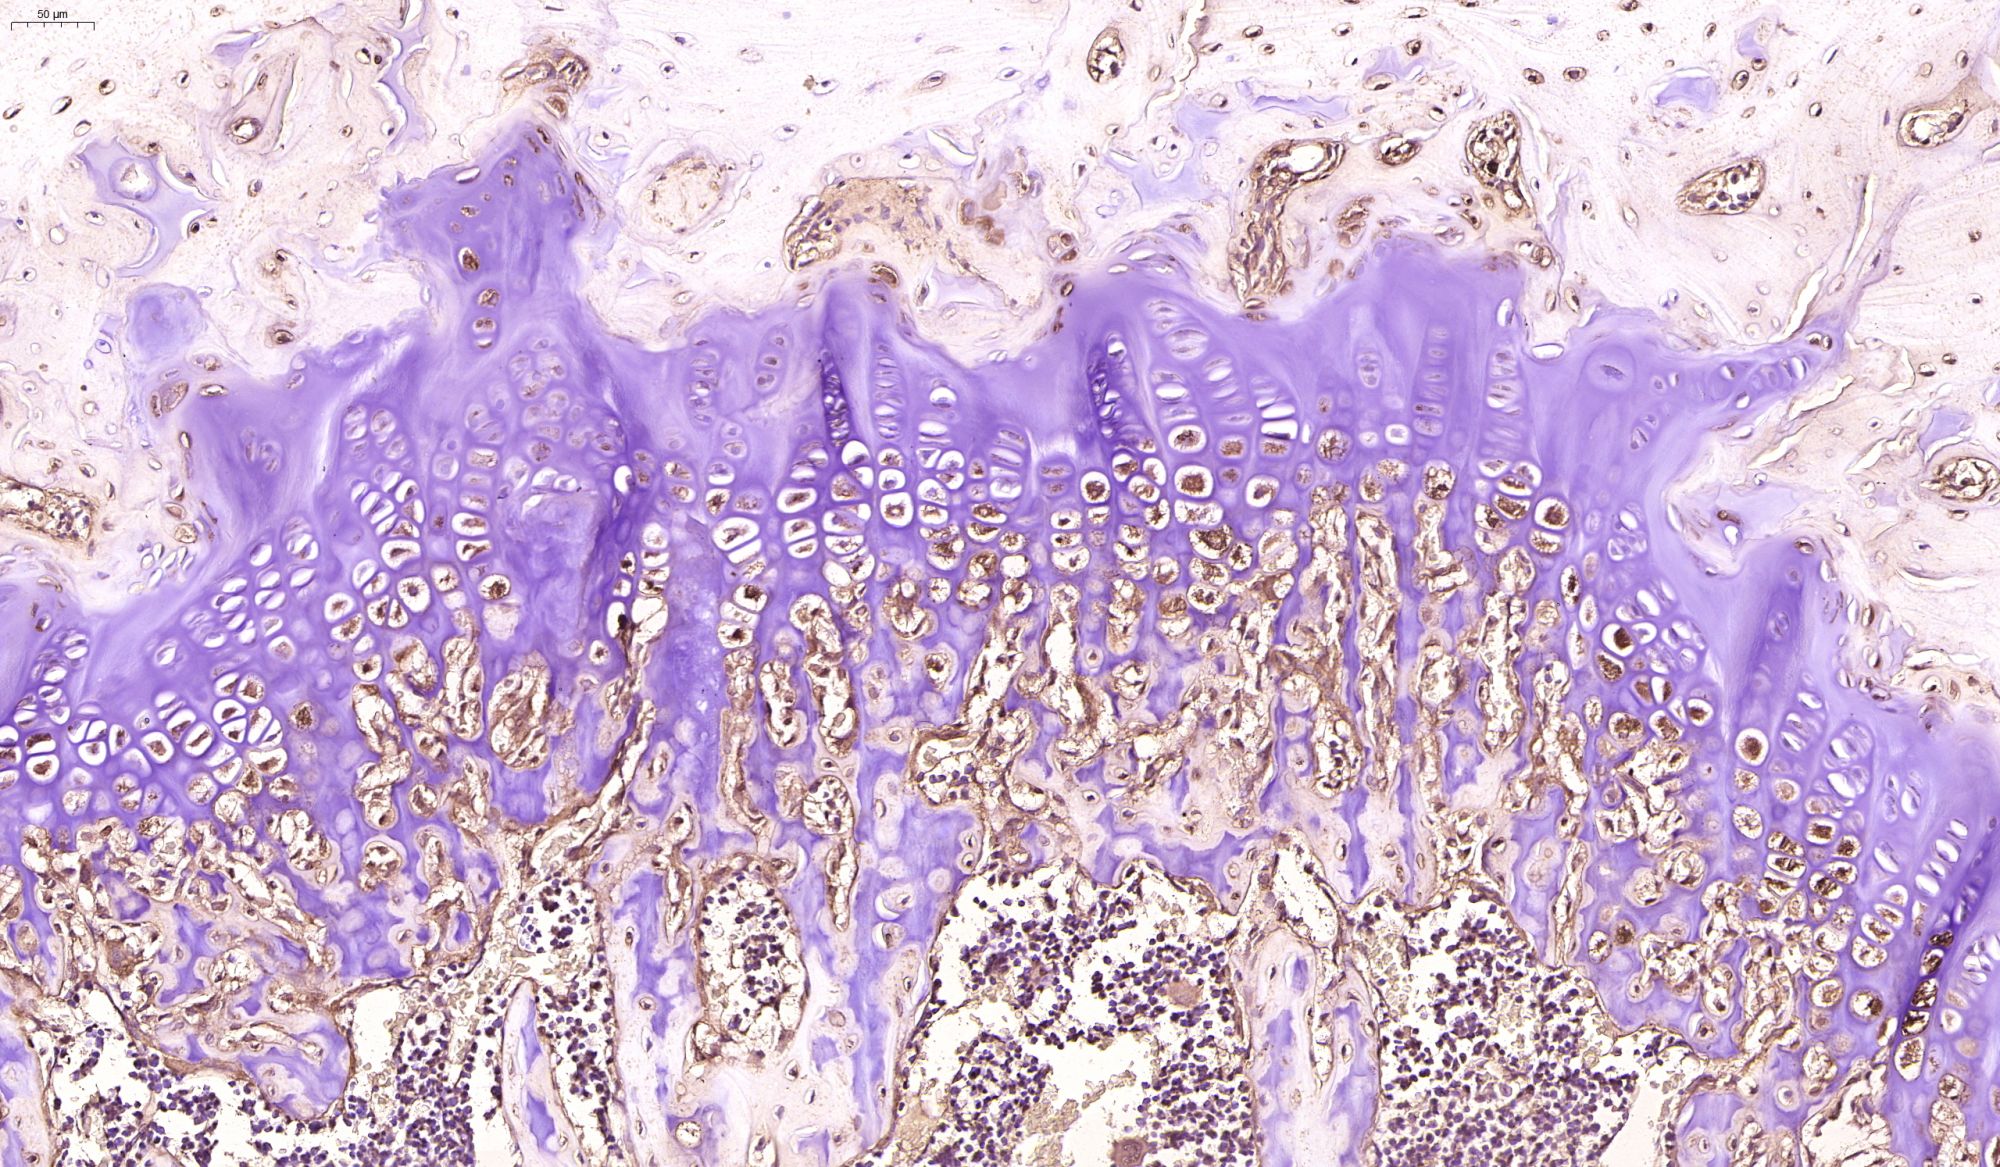

優(yōu)秀案例(免疫組化)